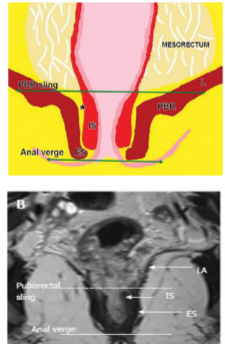

直肠壁黏膜层 T2WI 显示为低信号线;黏膜下层显示为厚度不均匀稍高信号;内侧环肌层和外侧纵肌层构成固有肌层,两者均为线状低信号,中间可有高信号脂肪层分隔开。

直肠系膜 (mesorectum): 直肠周围疏松结缔组织,包括脂肪组织、淋巴组织和血管神经。

直肠系膜筋膜 (mesorectalfascia,MRF): 包绕直肠系膜的固有筋膜就是 MRF。

肛门括约肌复合体

肛管被肛门括约肌复合体围绕,肛门括约肌复合体由互相重叠的两层肌肉构成。

肛管直肠结合部,直肠固有肌层变化,

环形肌变厚形成内括约肌。

外括约肌复合体由肛提肌最下部,耻骨直肠肌和外括约肌组成。

低位肛管中两个括约肌形成明显的括约肌间隙。